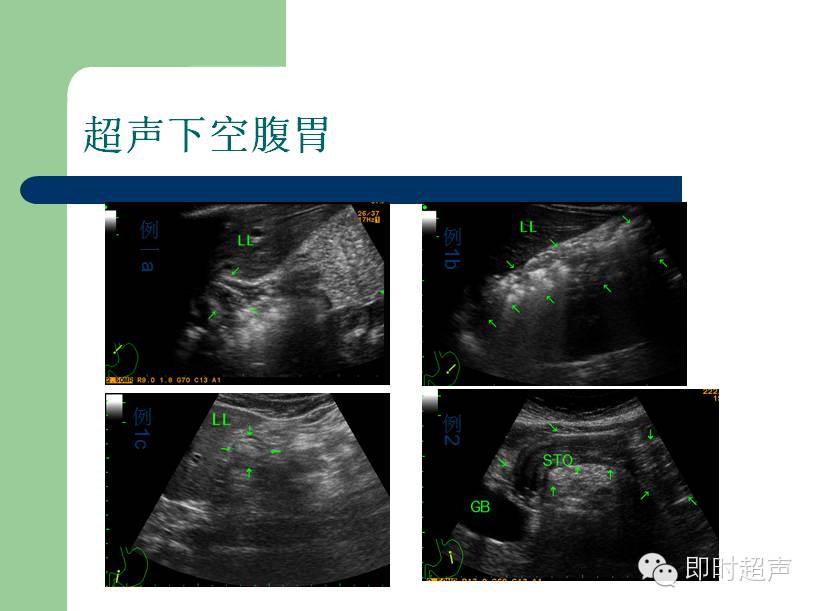

超声下的胃

来源:即时超声